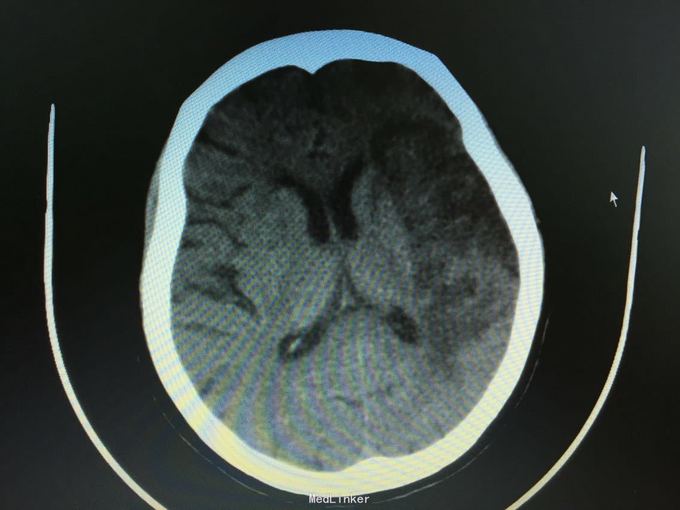

主诉:突发左侧肢体无力伴意识障碍2.5小时。 现病史:患者于2.5小时前突发左侧肢体无力,左侧肢体完全不能动,伴有意识障碍,急诊头CT显示多发脑梗死,为进一步诊治入院。 既往史:高血压,冠心病支架后,阵发房颤。

昏睡,完全混合性失语,双眼向左侧凝视,右侧肢体肌力0级,右侧病理征阳性。 头CT见多发陈旧小梗死。

诊断:大脑半球大面积脑梗死 治疗:抗血小板,脱水,降脂等,抗凝预防下肢静脉血栓

目前住院10余天,意识清楚,但仍遗留左侧肢体肌力0级,混合性失语等严重功能残疾。复查CT显示为左侧大脑半球大面积脑梗死。 讨论:对于高龄,大面积脑梗死患者,时间窗内是否溶栓?静脉还是动脉溶栓?